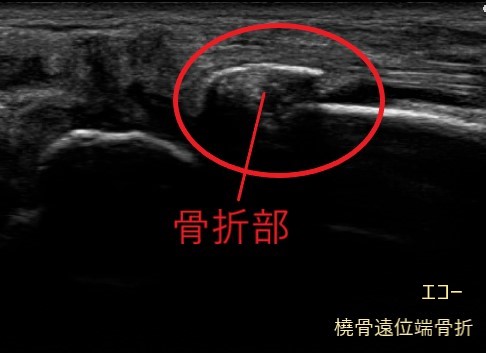

超音波(エコ-)検査は、骨・靭帯・筋肉・腱などの病態を診る検査装置です。

レントゲン画像には映りにくい筋肉や腱、靭帯などの状態に加え、骨の様子もあわせて確認できます。